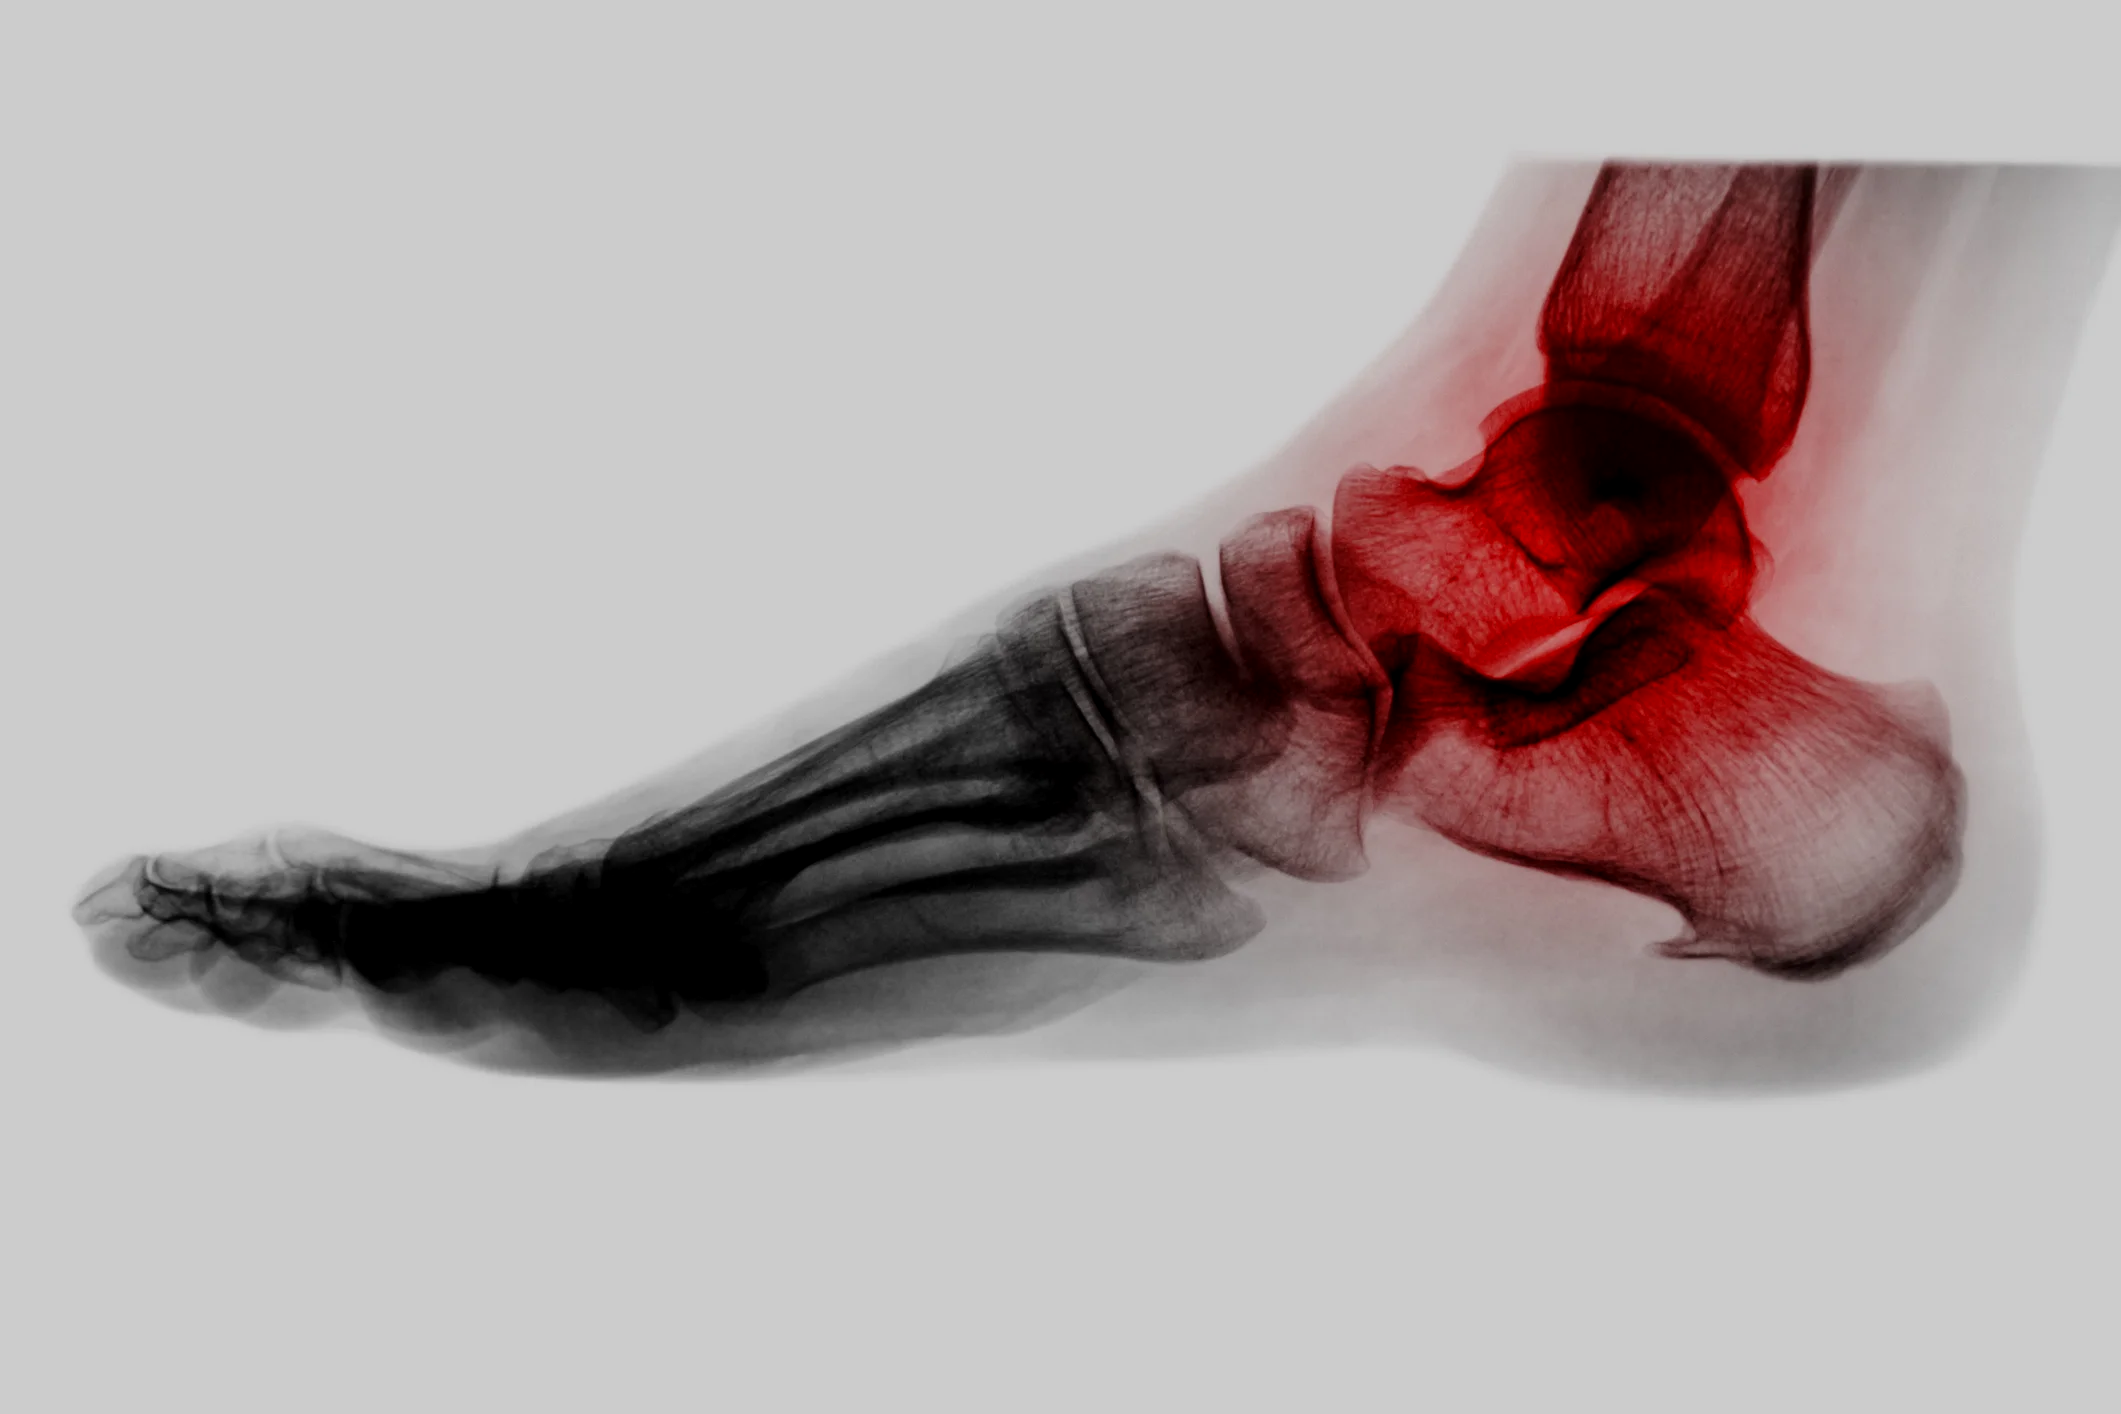

Hindfoot Arthritis